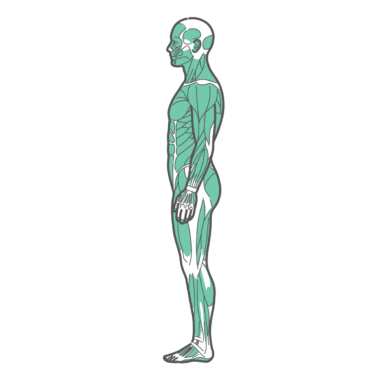

上半身・体幹 男性の全身筋肉図・人体解剖図のイラスト(側面・横向き)